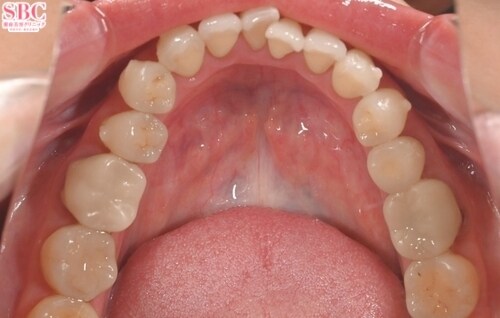

施術前

「前歯の捻じれ、歯の重なりがきになる」とのことでインビザラインモデレートにて治療したお写真になります★約7か月ほどできれいに並びました!マウスピース矯正は一日20時間以上マウスピースを使用し1週間?10日位の交換で進めていきます。スペースが足りない場合はIPR(歯と歯の間を削ってスペースを作る処置)やゴムかけが必要になる場合がございます。どのプランが適切かカウンセリング時にご説明させていただきます★ご興味ある方は是非カウンセリングにいらしてくださいませ。お待ちしております!

「前歯の捻じれ、歯の重なりがきになる」とのことでインビザラインモデレートにて治療したお写真になります★

約7か月ほどできれいに並びました!

マウスピース矯正は一日20時間以上マウスピースを使用し1週間?10日位の交換で進めていきます。

スペースが足りない場合はIPR(歯と歯の間を削ってスペースを作る処置)やゴムかけが必要になる場合がございます。

どのプランが適切かカウンセリング時にご説明させていただきます★